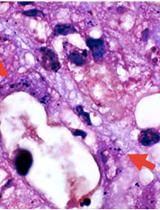

African swine fever virus (ASFV), a member of Asfarviridae family, causes a highly contagious and lethal hemorrhagic fever, namely African swine fever (ASF) in wild boars and domesticated pigs. The mature virus particle (virion) has 175-215 nm diameter, with a lipid bilayer enclosing an icosahedral capsid and a 180-190 kilobase pairs long double-stranded DNA genome. The virus causes a wide-spectrum of symptoms including highly lethal to sub-clinical, depending on host characteristics and the virus strain (Tulman et al., 2009). Preliminary diagnosis of ASFV in clinical samples (typically whole blood) is performed using real-time polymerase chain reaction (rt-PCR), which detects pieces of viral genome but active infection, the latter is confirmed via virus isolation and further downstream analyses, such as whole genome sequencing. Before the publication of our recent work identifying MA-104 cells as a substrate for ASFV detection (Rai et al., 2020), infectious virus detection could only be performed in primary macrophage cultures prepared from fresh pig blood. This protocol uses commercially available African green monkey cell line MA-104 (Whitaker and Hayward, 1985) as a substitute for detection and quantification of infectious ASFV either by hemadsorption (HA) or by staining with specific antibody for ASFV.